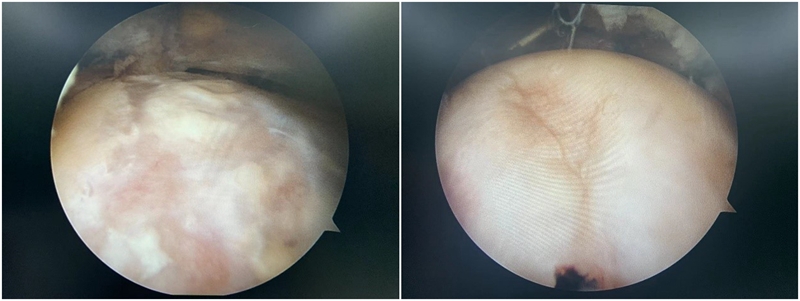

3.软骨损伤的处理:髋关节撞击综合征患者除了常常导致髋关节盂唇的损伤之外,还常常造成髋关节软骨的损伤,而且髋关节软骨损伤的部位也常常发生在髋臼的前方。目前对于任一关节的软骨损伤治疗都是难点,对于髋关节这样的负重关节更是如此。对于怀疑存在软骨损伤患者,则应早期进行手术治疗,尽可能避免髋关节退变的结局。

图11 撞击导致软骨损伤

病例,王X,女,32岁,反复活动后髋关节疼痛6月余,休息能缓解,诊断为髋关节撞击综合征合并盂唇损伤,规律保守治疗后无效,行髋关节镜下手术。

图12 术中